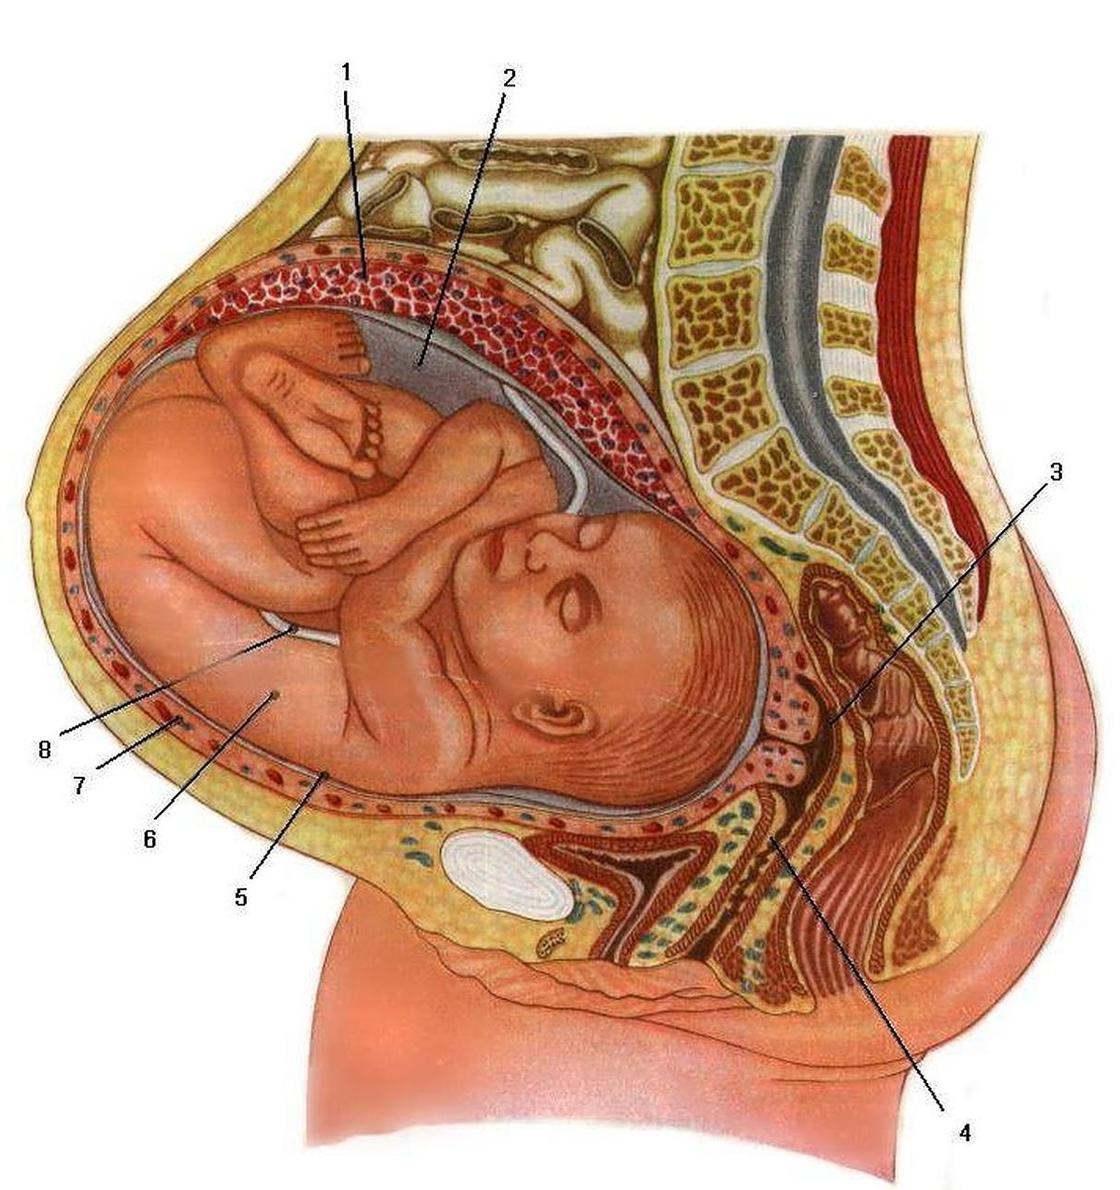

Физиология беременности: строение органов

Раздел: Моменты озарения